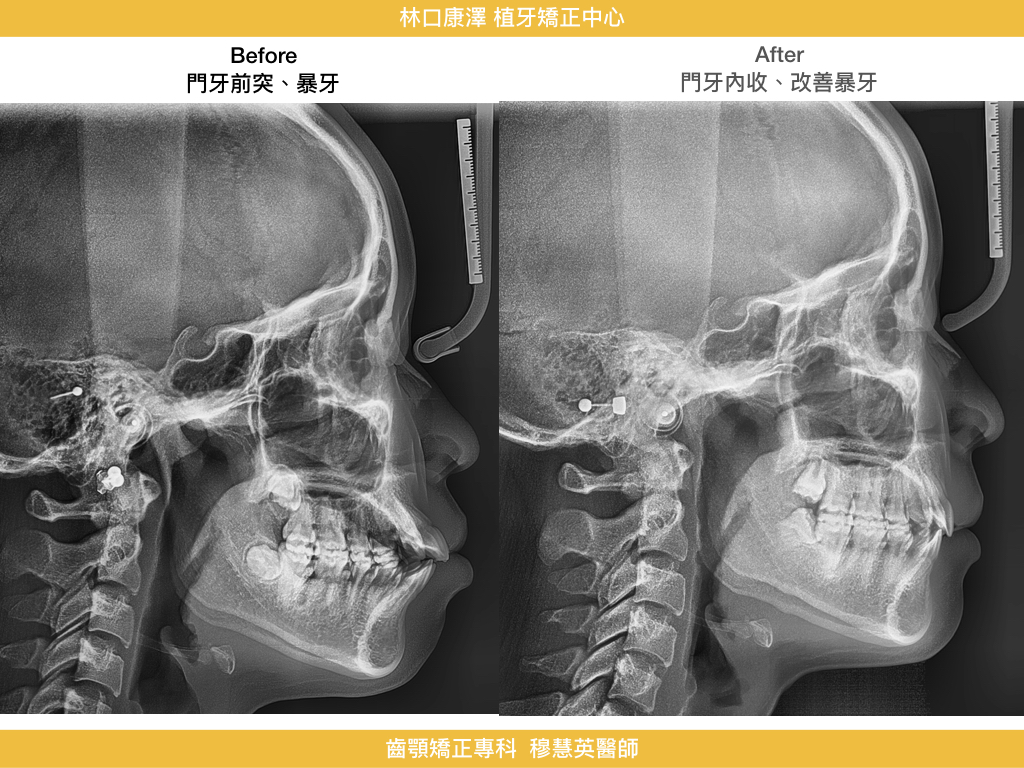

改善暴牙、嘴唇閉合困難與臉型突出,找回柔和側臉與自信笑容!

今天來分享一位非常漂亮的年輕女性患者,她有個很困擾自己的問題--暴牙。門牙往外凸,嘴唇無法輕鬆閉起來,側臉看起來有點暴,雖然五官本來就很精緻,但總覺得臉型不夠柔和、笑起來不夠好看。對許多患者來說,「暴牙」不只是牙齒排列的問題,更可能影響到整體臉型比例、臉部表情和笑容。

這是一個改善外觀的經典矯正案例,在康澤牙醫由矯正專科穆慧英醫師治療下,透過拔牙空間內收前牙,不只處理了牙齒排列,更徹底解決了唇形與臉型比例的長期困擾。成年女性在意的,不只是矯正後的牙齒整齊,而是從正面到側面,每一個角度都能展現自信與自然美感。

• 門牙順利內收:前突狀況明顯改善,口唇不再外翻

• 嘴唇可自然閉合:靜態時不再緊繃,表情更放鬆柔和

• 側臉輪廓變直:由原本的凸面型轉為柔和直線型,臉型更協調